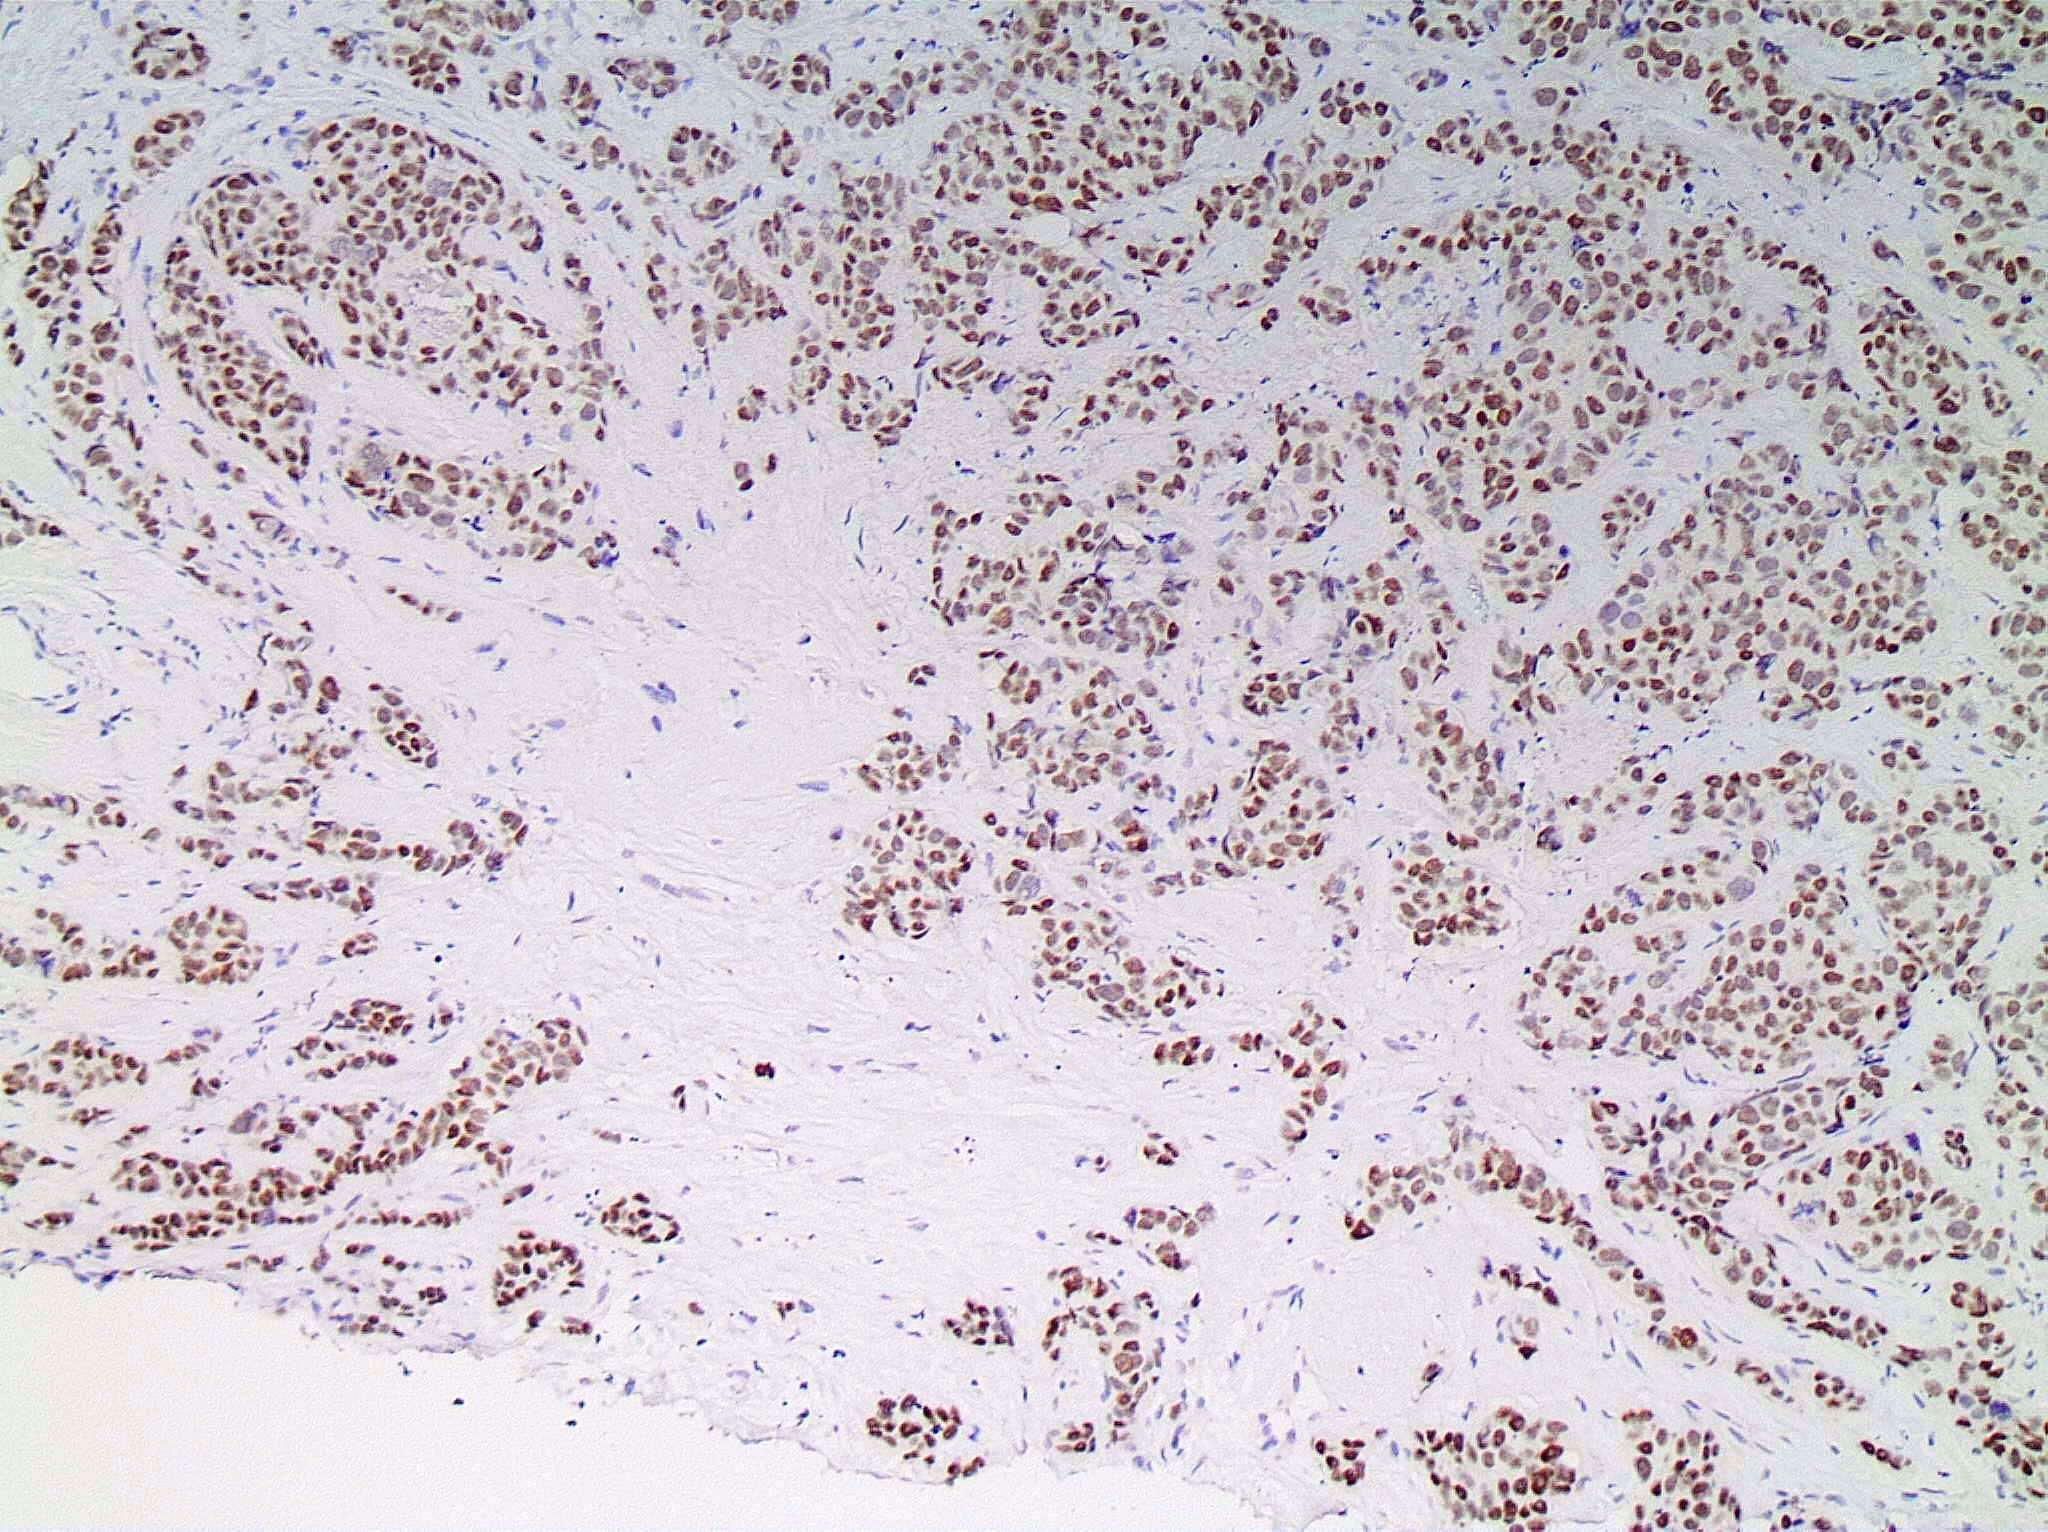

Microscopic (histologic) images

Contributed by Julie M. Jorns, M.D., Kristen E. Muller, D.O., Gary Tozbikian, M.D. and Emad Rakha, M.D.

Positive stains

- Luminal low molecular weight cytokeratins (CK8 / 18, CK19 and CK7 and pancytokeratins such as AE1 / AE3, CAM 5.2, MNF-116), EMA, E-cadherin, p120, ER (60 - 80%), PR (50 - 70%), HER2 (15 - 20%) (Am J Clin Pathol 2006;125:377)

- GATA3 (~91 - 100% of hormone receptor positive breast cancers, ~43 - 66% in triple negative breast cancer) (Hum Pathol 2014;45:2225, Hum Pathol 2015;46:1829)